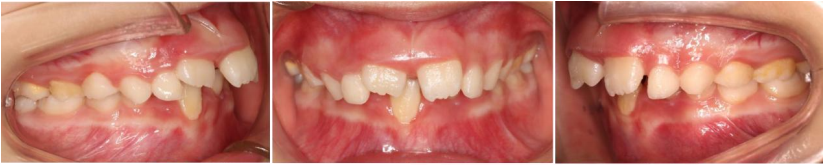

这位6岁的小朋友主诉嘴凸、没下巴、牙齿不齐,家长的早矫意识比较强,决定让小朋友及时进行早期矫正干预。

通过牙片资料检查孩子有骨性II类倾向,重度深覆合深覆盖,牙齿存在散在间隙。第一阶段佩戴隐形牙套,隐形矫正结束后,上颌内收,颏部前伸,侧貌形态改善良好,前牙达到正常覆合覆盖。

后续开展第二阶段时,将采用Grace定制化硅胶牙套,精细调整匹配上下颌弓形,整平颌平面,利用孩子生长发育潜力,继续引导下颌向前。